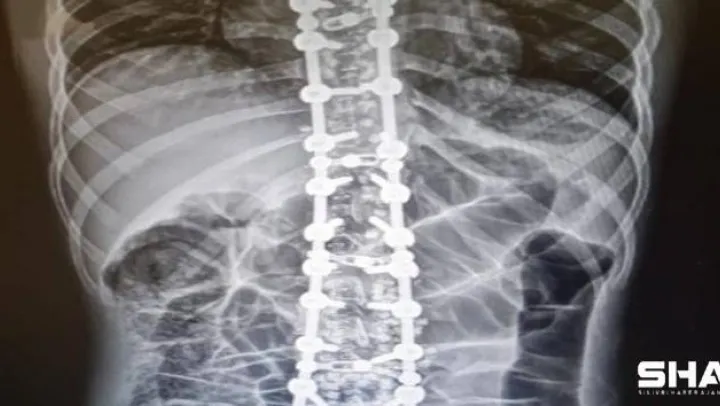

Osteopati vücudun her yerine uygulanabileceğini ancak en sık omurga problemlerinde kullanılmakta olduğunu ifade eden Özyurt, sözlerini şu şekilde sonlandırdı:'Omurganın patolojik olarak saydığımız faset eklem kitlenmesi, omurgayı dik durmasını sağlayan kasların spazmı ve diğer omurga problemlerinde güvenle kullanabileceğimiz yöntemler bulunmaktadır. Duruş bozuklukları, omurga ve kas- iskelet sistemi hareket fonksiyon bozuklukları, omurga disk kaymaları, kuyruk sokumu problemleri, eklem sertliği, migren, gerilim tipi baş ağrısı, uyku bozuklukları, iç organ kaynaklı kas-iskelet sitemi ağrıları gibi çeşitli ve birçok hastalıkta osteopati kullanılabilir. Osteopatinin tedavi süresi probleme, yaşa ve kişiye göre değişebilmektedir.'